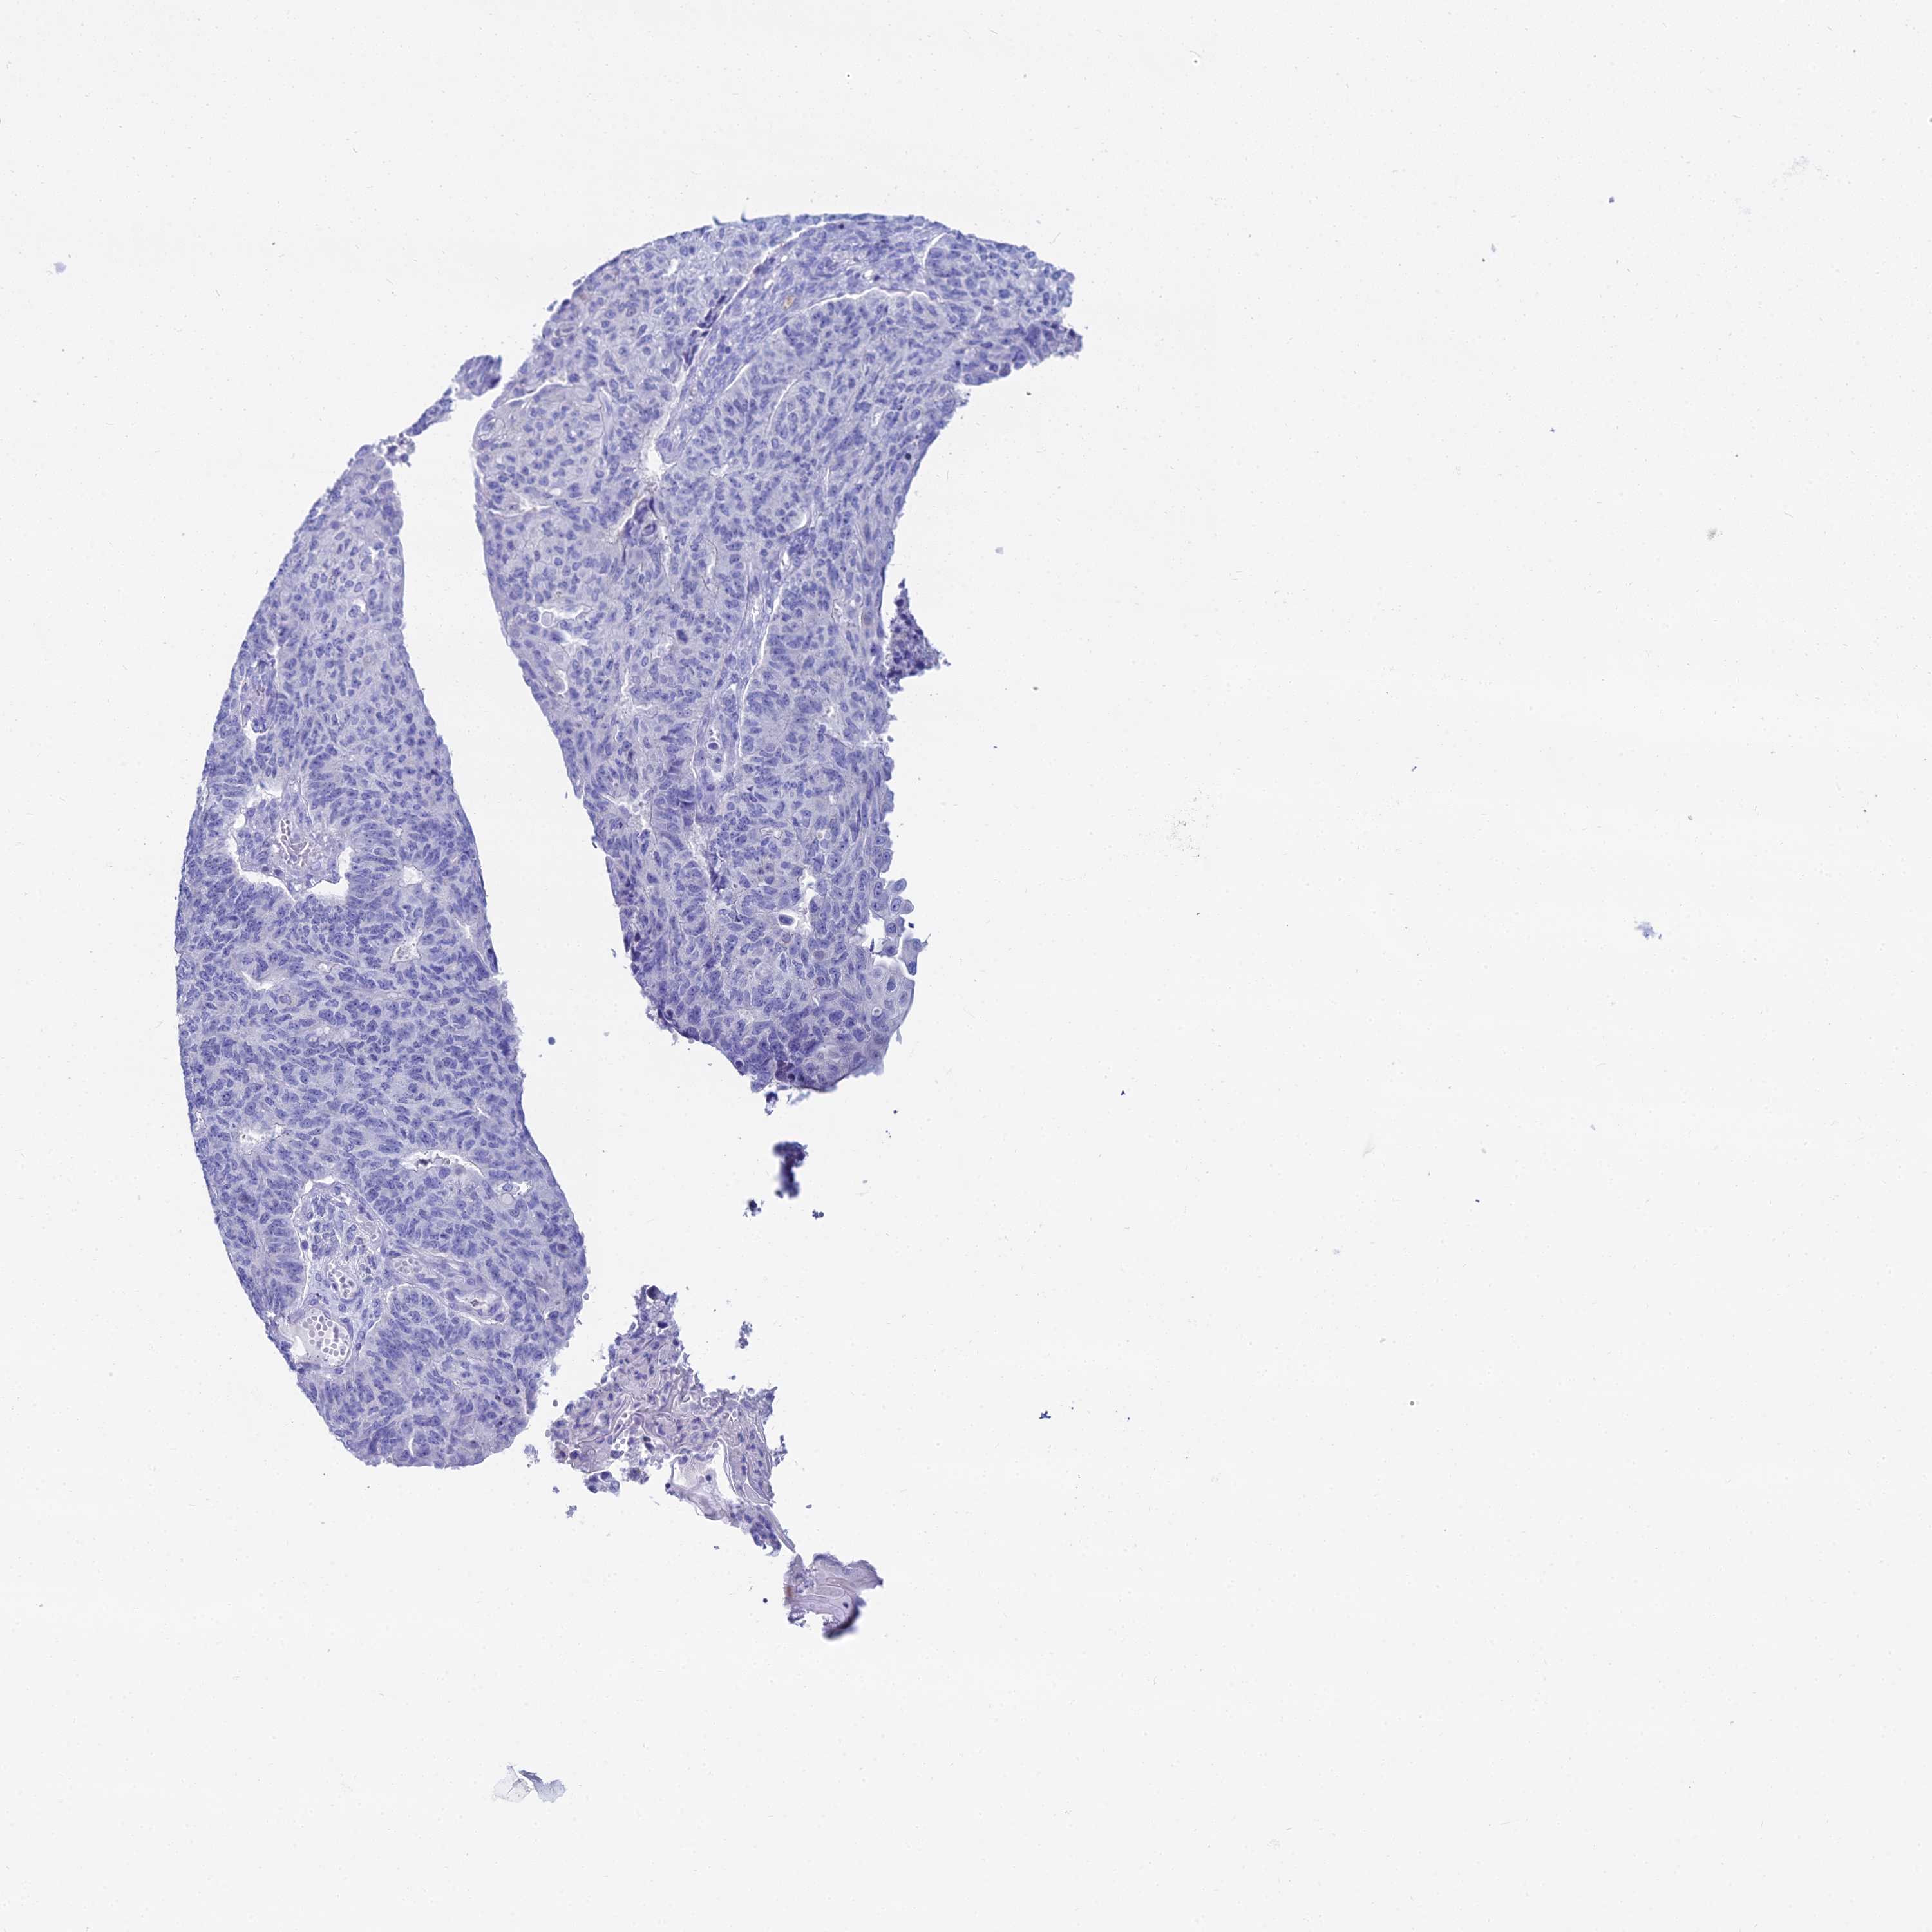

ENDOMETRIAL CANCER - Protein expressioni

A mouse-over function shows sample information and annotation data. Click on an image to view it in a full screen mode. Samples can be filtered based on level of antibody staining by selecting one or several of the following categories: high, medium, low and not detected. The assay and annotation is described here.

Note that samples used for immunohistochemistry by the Human Protein Atlas do not correspond to samples in the TCGA dataset.

Antibody stainingi

Antibody staining in the annotated cell types in the current human tissue is reported as not detected, low, medium, or high, based on conventional immunohistochemistry profiling in selected tissues. This score is based on the combination of the staining intensity and fraction of stained cells.

Each image is clickable and will lead to virtual microscopy that enables deeper exploration of all samples and also displays staining intensity scores, fraction scores and subcellular localization as well as patient and tissue information for each sample.

Antibody HPA043285

Antibody HPA052504

Staining

High

Medium

Low

Not detected

Intensity

Strong

Moderate

Weak

Negative

Quantity

>75%

75%-25%

<25%

None

Location

Nuclear

Cytoplasmic/membranous

Cytoplasmic/membranous,nuclear

Adenocarcinoma, NOS

Adenocarcinoma, metastatic, NOS

Carcinoma, NOS